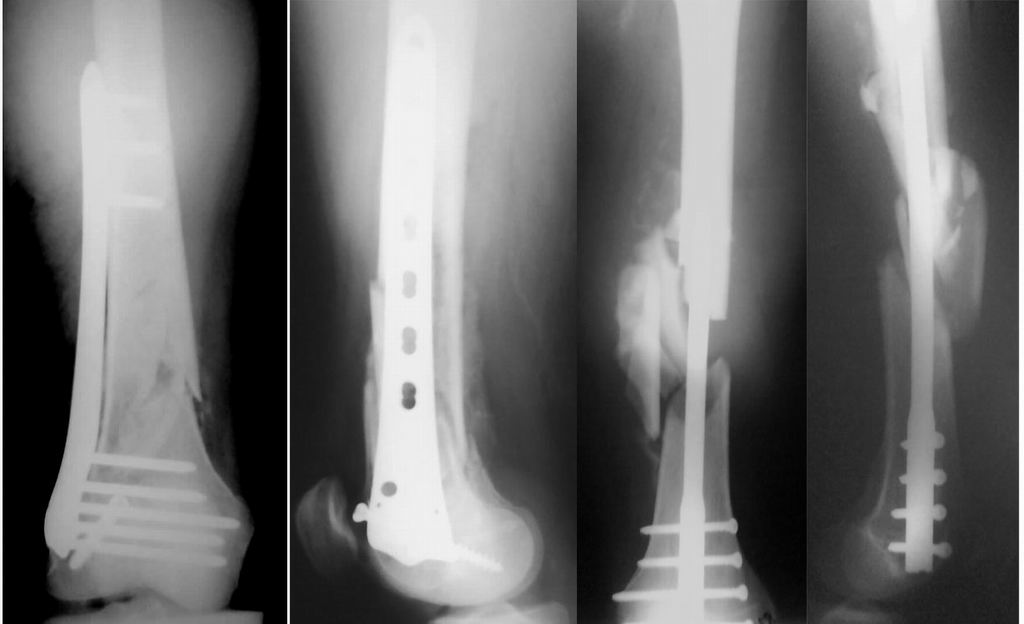

Уважаемые коллеги! От имени Алексея Смирнова всем спасибо за обсуждение. Больной прооперирован. Снимки в приложении.

Мы бы не стали открывать, такие переломы срастаются, хотя бы и с краевым дефектом. То есть если удалять стержень потом, то сильно попозже обычного. В приложении пример. Сразу после операции и через 11 мес. Понятное дело, пациент к тому времени давно и не хромал, и функция колена была полная.